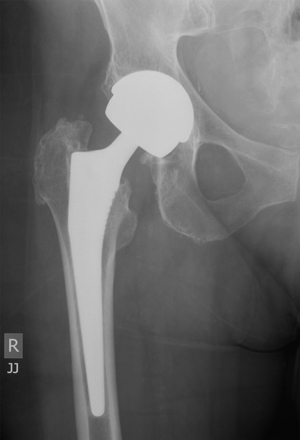

The patient’s original hip replacement had been done in 2006 with an ASR (articular surface replacement) hip prosthesis (ASR XL Acetabular Hip System [DePuy Orthopaedics, Warsaw, Ind, USA]), comprising a large-diameter metal (cobalt and chromium) cup with a large modular metal head on a titanium Corail stem (Box). A revision total hip replacement was performed in March 2011, principally because of her systemic symptoms and elevated cobalt and chromium levels. The ASR metal cup and head were removed and the stem retained. Her acetabulum was revised with an all-polyethylene cemented cup and the head was changed to a ceramic one. At the time of surgery, 30 mL of turbid fluid was aspirated from the joint and debridement of metal stained tissue was undertaken. The concentration of cobalt in the joint fluid was 4218 nmol/L and chromium was 217 000 nmol/L. Cerebrospinal fluid (CSF) collected at surgery showed a cobalt level of 9 nmol/L and a chromium level of 13 nmol/L (no reference ranges for these in CSF), showing that the ions had crossed the blood–brain barrier.

Total hip replacement is generally a successful operation, with a long clinical history of good outcomes. Conventional total hip prostheses consist of a metal head that fits into a polyethylene cup. Concerns have been raised, particularly in younger patients, that the plastic cup suffers wear and tear with time and may require revision. In an attempt to decrease wear at the interface of the articulation, metal-on-metal bearings (Box), composed of cobalt and chromium, have gained widespread popularity and have been used extensively, particularly in the United States.